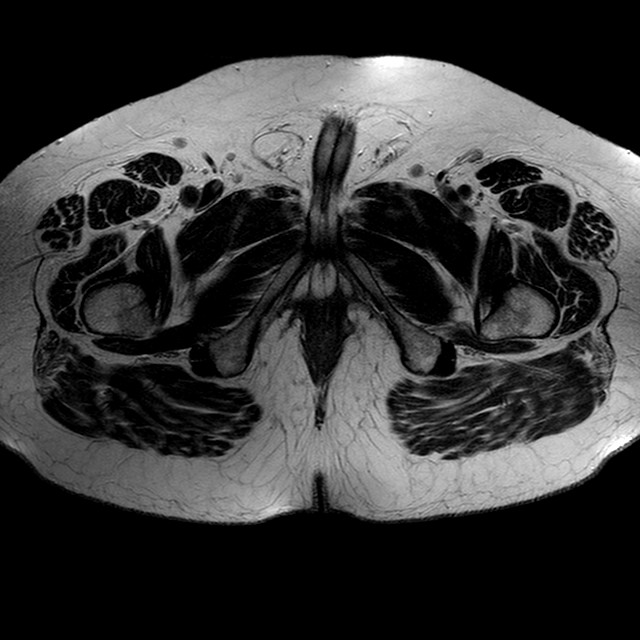

Esami: RMN BACINO

T2w TSE

Evidenti e simmetriche alterazioni osteofitosiche in regione coxo femorale con riduzione delle rime articolari. Degenerazione completa del cercine glenoideo. Non attuali segni di versamento articolare. Non segni di edema osseo che escludono attuale algodistrofia od osteonecrosi. Lieve e simmetrica riduzione del trofismo della muscolatura glutea.